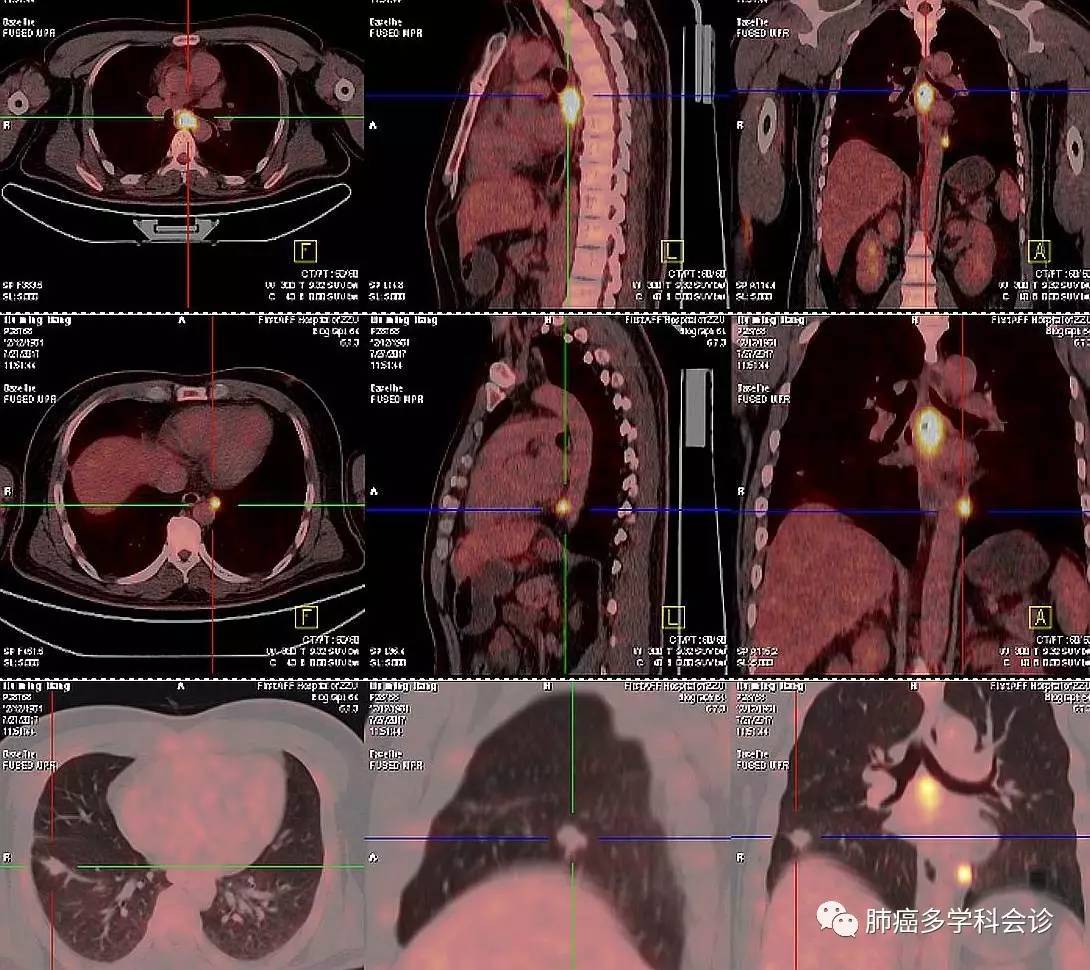

本周四下午,向与会的会诊专家们展现了一位年轻男性患者的 PET-CT 图像(2017-07-27),下图集中了患者体内的所有被发现的肿瘤病变。

部分参加专家认为是食管癌肺转移,也有人认为同时患有食管癌和肺癌。

其实是晚期肺癌,治疗 1 年后发现食管转移!